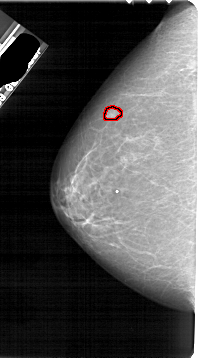

A_1884_1.RIGHT_CC

RIGHT_CC LINES 5416 PIXELS_PER_LINE 2746 BITS_PER_PIXEL 12 RESOLUTION 43.5 NON_OVERLAY

FILE: A_1884_1.LEFT_MLO.OVERLAY

TOTAL_ABNORMALITIES 1

ABNORMALITY 1

LESION_TYPE MASS SHAPE LOBULATED MARGINS OBSCURED

ASSESSMENT 4

SUBTLETY 3

PATHOLOGY BENIGN

TOTAL_OUTLINES 1

BOUNDARY